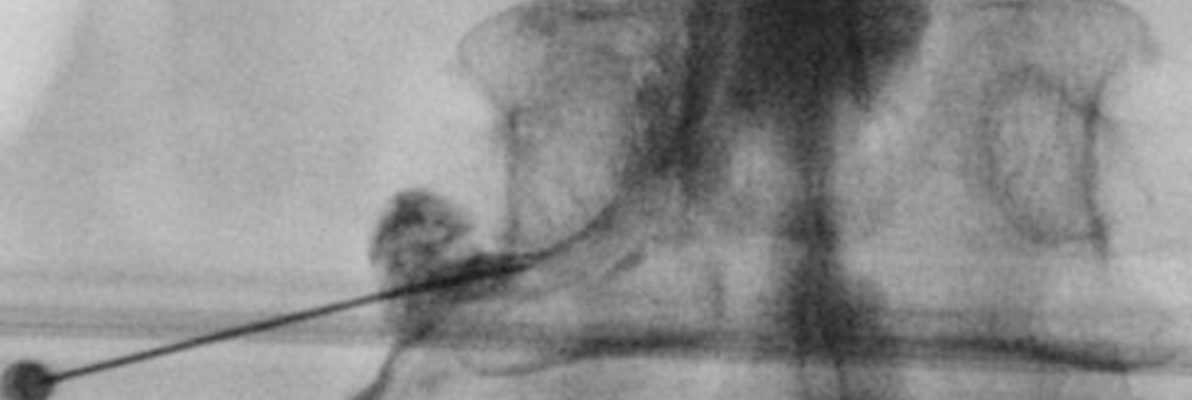

엑스레이 유도 신경차단술은 전자기파를 사용하여 신체 내부 구조를 2D 형태로

시각화하여 신경의 정확한 위치를 확인하고 통증을 유발하는 신경의 활동을

차단하거나 제한하여 통증을 완화시키는 방법입니다.